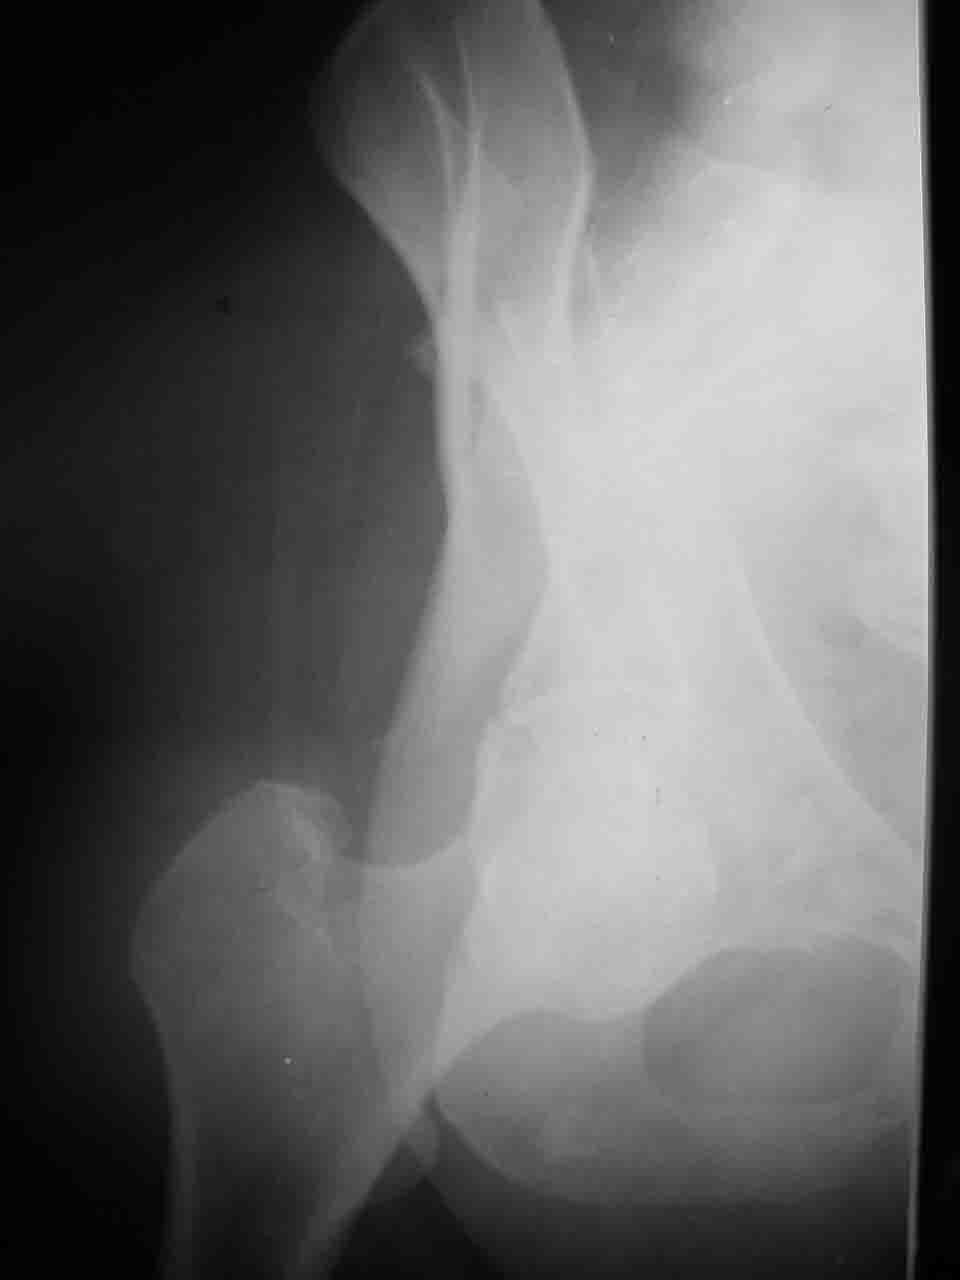

Причиной обращения к сообществу были возникшие непосредственно после операции сомнения и разочарования полученным качеством репозиции: а надо ли было трогать перелом вообще, репозиция передней колонны технически была очень сложна для меня, хотя реконструкции была в той же последовательности, что Д-р А.В.Рунков рекомендовал, в какой-то момент безуспешных манипуляций стал думать о *вторичной конгруэнтности*, которую не так давно обсуждали на

форуме и скелетном вытяжении. С репозицией и фиксацией задней колонны и отдельно задне-верхней стенки впадины проблем не возникло. Послеоп. Рг граммы в приложении. Если возникнут какие-либо дополнения или поправки - был бы признателен.

А какой отдел вертлужной впадины более важен передний или задний? Чем был обусловлен выбор доступа к суставу? Проще говоря, почему вы пошли передним доступом на двухколонный перелом? Мне понятны ваши сомнения, когда не удется сделать все что хотелось бы. В данном случае доступ должен быть чрезвертельным боковым (как и советовал Рунков) или двумя доступами.